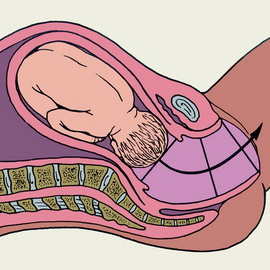

1. Відбувається вставляння голівки плоду у вхід малого тазу.

2. згинання голівки плоду. Під впливом внутрішньоматкового тиску верхня частина хребта плода згинається таким чином, що підборіддя наближається до грудної клітки, а потилицю впирається вниз, у вході в малий таз.

3. Проходження головки в порожнину малого таза.

4. Внутрішній поворот голівки плоду.

Завдяки сутичок відбувається необхідне для вигнання плоду розкриття шийки при пологах: скорочення матки починаються в області її дна, захоплюють всю мускулатуру її тіла до нижнього сегмента. Вважають, що в матці існує домінуючий осередок збудження, що розташовується найчастіше в її правому куті, звідси хвиля скорочень поширюється на всю мускулатуру і йде в низхідному напрямку. У нижньому сегменті матки гладких м'язових волокон менше, тому під час пологів він стоншується і розтягується. Кожна сутичка розвивається в певній послідовності. Скорочення матки поступово наростають, досягають найвищого ступеня, а потім відбувається розслаблення мускулатури, що переходить в паузу. На початку пологів кожна сутичка триває 10-15 секунд, до кінця в середньому 1,5 хвилини (60-80 секунд). Паузи між ними на початку пологів тривають 10-15 хвилин, а потім стають менш тривалими. До кінця періоду вигнання плода при пологах сутички настають через 2-3 хвилини і навіть частіше.З початку появи регулярних переймів, є Той, що виганяє родовими силами, плід починає відчувати внутриматочное тиск. Частина навколоплідних вод спрямовується під дією тиску в нижній відділ матки до перешийку, який все більше наповнюється. Плодовий міхур впроваджується в канал шийки матки, що сприяє згладжування і прогресуючого розкриття зіву шийки матки. Під час сутичок у м'язах тіла матки відбуваються скорочення м'язових волокон - контракції і зміщення скорочуються м'язових волокон, зміна їх взаємного розташування - ретракція. Ці зміщення зберігаються і в інтервалах між переймами.

При повному розкритті при пологах маточного зіва порожнину матки і піхву складають родовий канал. При ретракції матки розтягується не тільки шийка, а й нижній сегмент. При наростанні сутичок формується контракціонное кільце. Головка, охоплена маткою, ділить навколоплідні води на передні і задні (внутрішній пояс дотику). Обсяг передніх вод становить близько 300 мл, а задніх - 1 000мл. Внаслідок збільшення внутрішньоматкового тиску під впливом наростаючих сутичок посилюється вплив на плодовий міхур, вклинюються в шийного каналу.